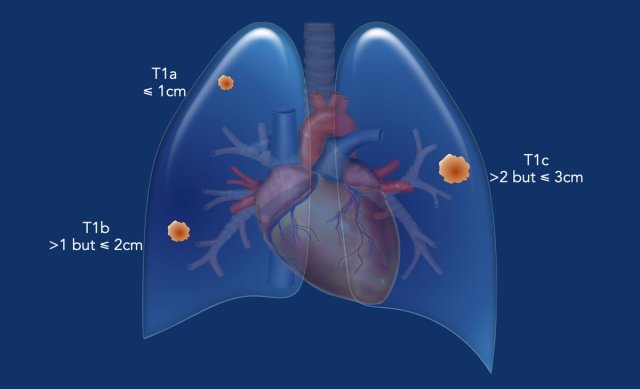

T1-tumor

• ≤ 3 cm, surrounded by lung/visceral pleura, or in lobar or more peripheral bronchus.

• T1mi  Minimally invasive adenocarcinoma.

• T1a  ≤ 1 cm.

• T1b  >1 cm but ≤ 2 cm.

• T1c  >2 cm but ≤ 3 cm.

T1 tumor

A typical T1 tumor in the left lower lobe (23 mm, cT1c), completely surrounded by pulmonary parenchyma.